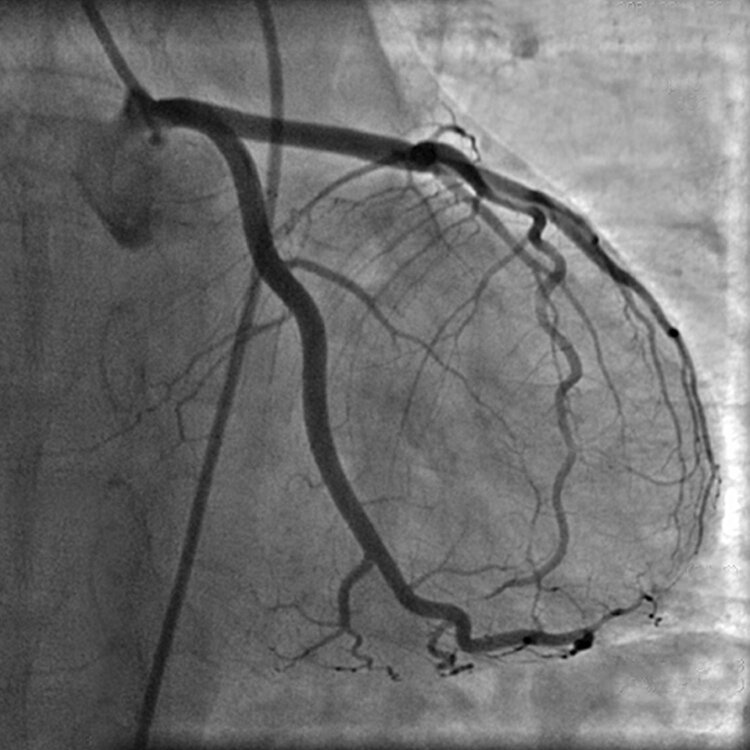

На фото представлены основные сосуды, питающие сердечную мышцу.

Коронарография представляет собой инвазивную методику визуализации проходимости венечных артерий сердца. Цель, поставленная перед данным методом, – это обследование коронарного дерева (сосудов, питающих сердечную мышцу), а также любых установленных ранее стентов и шунтов.

Проводится это для оценки анатомической и функциональной патологии (закупорка сосудов, наличие атеросклеротических бляшек, тромбов, врожденных аномалий и т.д.), наличия межкоронарных и внутрикоронарных коллатеральных сообщений, что может повлиять на распределение крови и питание ею миокарда.

Длительность процедуры занимает в среднем 30 минут, во время которых с использованием рентгенконтрастного вещества (обычно йодсодержащего) и под локальной анестезией производится серия снимков при помощи рентгенологического аппарата с высокой резолюцией. Это позволяет рассмотреть все сегменты коронарного артериального кровообращения вплоть до сосудов с диаметром 0.3 мм.